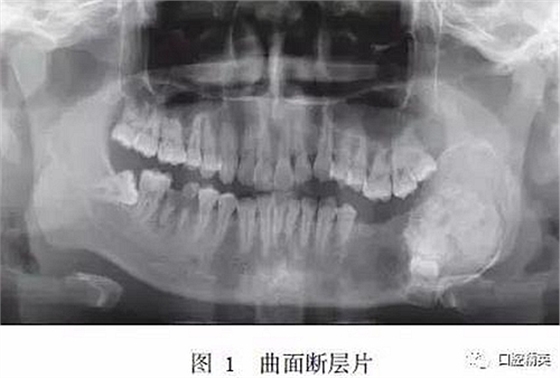

入院時專科查體:患者面型不對稱,開口度正常,開口型偏左側(cè)。左下頜膨隆明顯,范圍約5.0 cm×3.0 cm,向前延伸至D5根尖處,向后延伸至下頜升支,質(zhì)硬,觸之無乒乓樣感??趦?nèi)檢查示D5~D8缺失,左側(cè)頜下有一腫大淋巴結(jié),質(zhì)硬,活動,大小約1.5 cm×1.5 cm。曲面斷層片示:左下頜D4根尖區(qū)至左下頜升支乙狀切跡下方可見一異常高密度團塊影,團塊中心密度不均勻,病變邊緣光滑,周緣可見低密度條帶影包繞,D5~D8牙埋伏阻生于病變內(nèi),似不規(guī)則小牙體征象,病變區(qū)頜骨向頰舌向膨隆明顯,下頜神經(jīng)管受壓后向下移位(圖1)。

(1)影像學(xué)檢查。OF為境界清楚的單房性密度減低區(qū),病變中央常見不透光區(qū)。FD為病變區(qū)阻射性降低,呈磨玻璃樣改變,病變與周圍正常骨質(zhì)界限不明顯。本例影像學(xué)特征為左下頜骨局部可見異常高密度團塊影,團塊密度不均勻,可見牙樣結(jié)構(gòu),病變邊界清晰,符合OF的影像學(xué)改變。